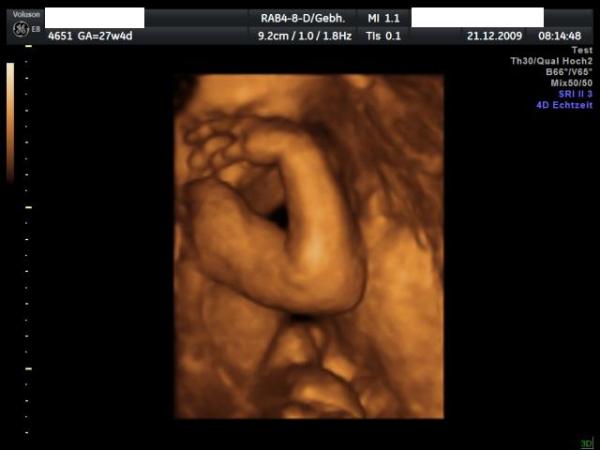

Hallo ihr Lieben, hatte gestern VU, Baby wiegt 900 g, liegt in SL. CTG war auch in Ordnung. Habe in 4 Wochen 1 kg zugenommen und insgesamt sind es nun fast 4 kg. Meine Ärztin meint es wird ein kleines Kind, wie der große Bruder, er hatte zur Geburt 2870 g und 47 cm kurz. Aber die kleinen holen das ja schnell wieder auf. Hänge euch ein Bildchen an, leider nur ein süßer kleiner Arm, mehr gute Sicht gab es gestern leider nicht.

Bild zu gestern VU - Forum für März - Mamis